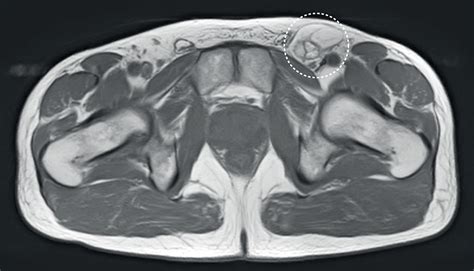

US image of the right groin shows fluid within an indirect inguinal... | Download Scientific Diagram

US image of the right groin shows fluid within an indirect inguinal... | Download Scientific Diagram from www.researchgate.net